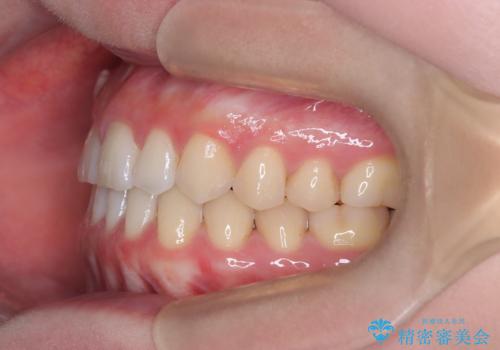

すきっ歯・切端咬合・空隙歯列|インビザラインで11ヵ月で治療完了

- すきっ歯と切端咬合(上下の前歯が先端で当たるかみ合わせ)を主訴にご来院された患者様です。

矯正検査を行った結果、非抜歯でインビザラインによる治療が可能と判断し、マウスピース矯正で改善を行いました。

11ヵ月で矯正治療が終了し、前歯の隙間も改善、見た目とかみ合わせも良好な状態となり、患者様にも大変ご満足いただけました。